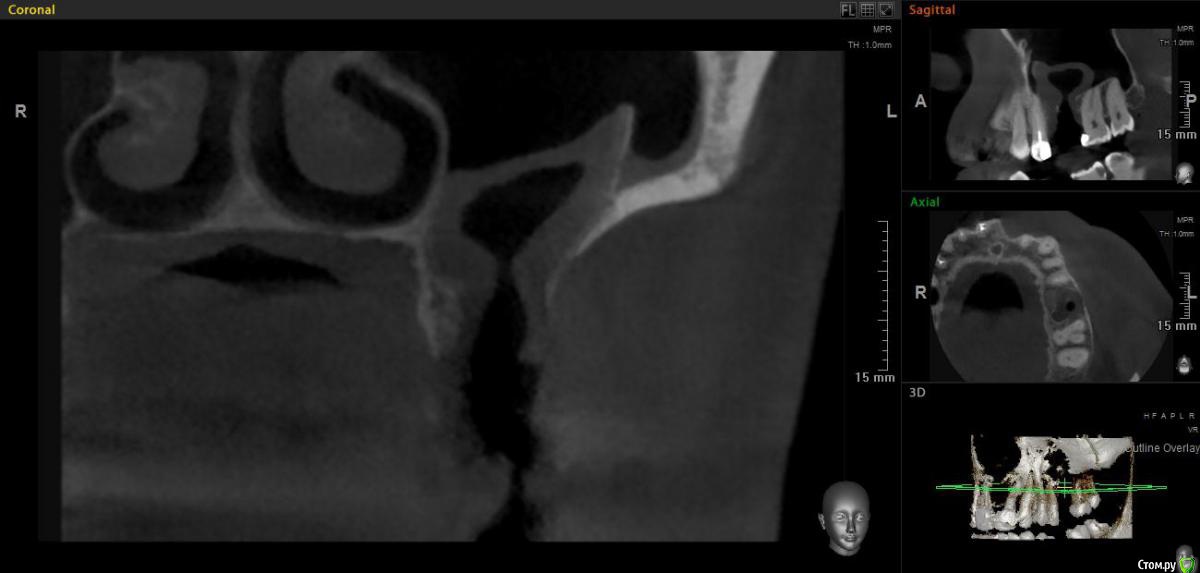

jm3300 Опубликовано 20 мая, 2019 Поделиться Опубликовано 20 мая, 2019 Добрый день. Пациент не мой, причины удаления, а так же о ходе удаления сказать ничего не могу. Известно лишь, что после удаления из лунки получили много зеленоватой жидкости. Удаляли с месяц назад. До сих пор имеется не сильно зияющая дырка. Нужно что то делать или просто ждать пока вторичным затянется. И если имплант планировать- ожидать ли там самостоятельного появления обьема кости? Ссылка на комментарий

L.E.S.I.K. Опубликовано 20 мая, 2019 Поделиться Опубликовано 20 мая, 2019 Я бы сделал ревизию через лунку, убрал оболочку кисты (похоже что она там осталась, или это эпителий врос - не важно) и провел бы закрытие небным лоскутом. При направлении в ЧЛХ есть вероятность, что наведут "разруху"(по Колддвел-Люк) и пациент получит проблему при дальнейшей реабилитации. З.Ы. На данных срезах не видно остиомеатальный комплекс- крайне желательно, чтобы он был не блокирован. 3 Ссылка на комментарий

Irouil Опубликовано 20 мая, 2019 Поделиться Опубликовано 20 мая, 2019 Я бы дождался эпитлизации (2 месяца), потом 2 варианта: В пазуху свистит - первым этапом разобщить, вторым этапом синусить В пазуху не свистит - сразу синусить Судя по наблюдаемой картине, соустье чистое 2 Ссылка на комментарий

Дмитрий М Опубликовано 21 мая, 2019 Поделиться Опубликовано 21 мая, 2019 месяц прошел, уже ничего не дождетесь, кость там не вырастет т.к. уже пошла эпителизация. так и останется не сильно зияющая дырка только вы видите клиническую картину, поэтому вам решать какой вариант лучше выбрать.в любом случае удалять кисту, оболочку, вероятно будет сообщение, которое необходимо закрывать и по ситуации готовиться к обоим вариантам по снимкам это скорее киста, (прослеживается кортикальная по контуру) 1 Ссылка на комментарий

Дмитрий Л. Опубликовано 21 мая, 2019 Поделиться Опубликовано 21 мая, 2019 Там уже есть сообщение с гайморовой. Возможно не функционирующее. Вяло текущий хронический воспалительный процесс. Ждать мало смысла. Если стремиться сделать всё как можно менее инвазивно, можно пойти по такому пути:1. Недельку попромывать соустье антисептиками. Воспаление стихнет. Десны добавится.2. Расскрыться. Аспирировать слизистую слюноотсосом. Кюретаж, всё через лунку. Если функционирующего соустья не было, оно появится.3. Небный лоскут, чтоб ушить соусье. Сосудосуживающие в нос, антибиотики. Ссылка на комментарий

jm3300 Опубликовано 21 мая, 2019 Автор Поделиться Опубликовано 21 мая, 2019 Ну по КТ и клинически сообщения с пазухой нет. Пациента,кроме наличия самой лунки, вообще ничего не беспокоит. Ссылка на комментарий